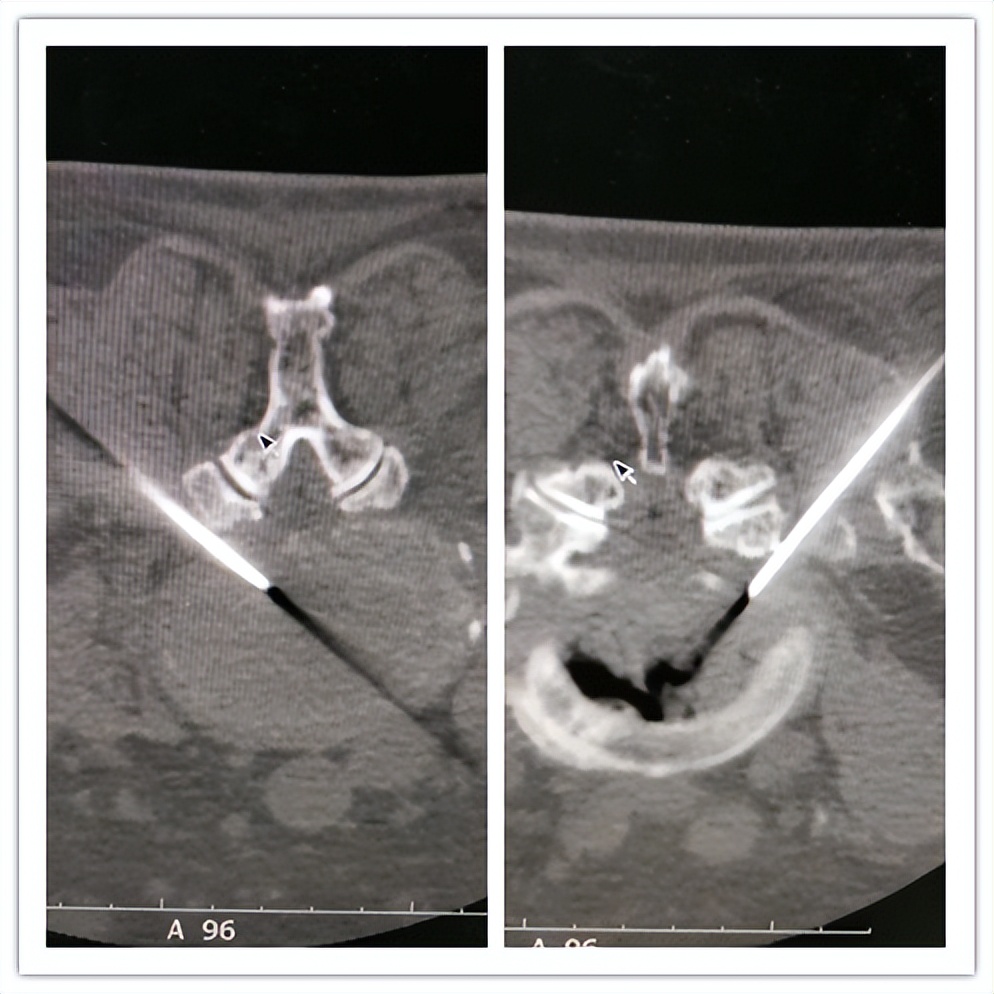

(腰椎间盘突出症:椎间孔镜下腰椎间盘髓核摘除)